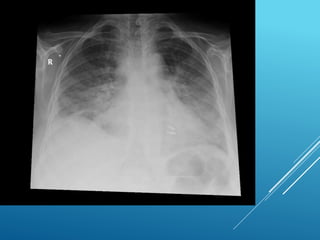

Q 13 - CXR

BNP RESULT

 Acute LVF/Acute Pulmonary Edema